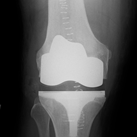

Below you see X-ray examples of patients with severe osteoarthritis of the hip before (Fig 1) and after (Fig 2) total hip replacement, and of the knee before (Fig 3) and after (Fig 4) total knee replacement that have been successfully treated under Mr Weitzel’s care.